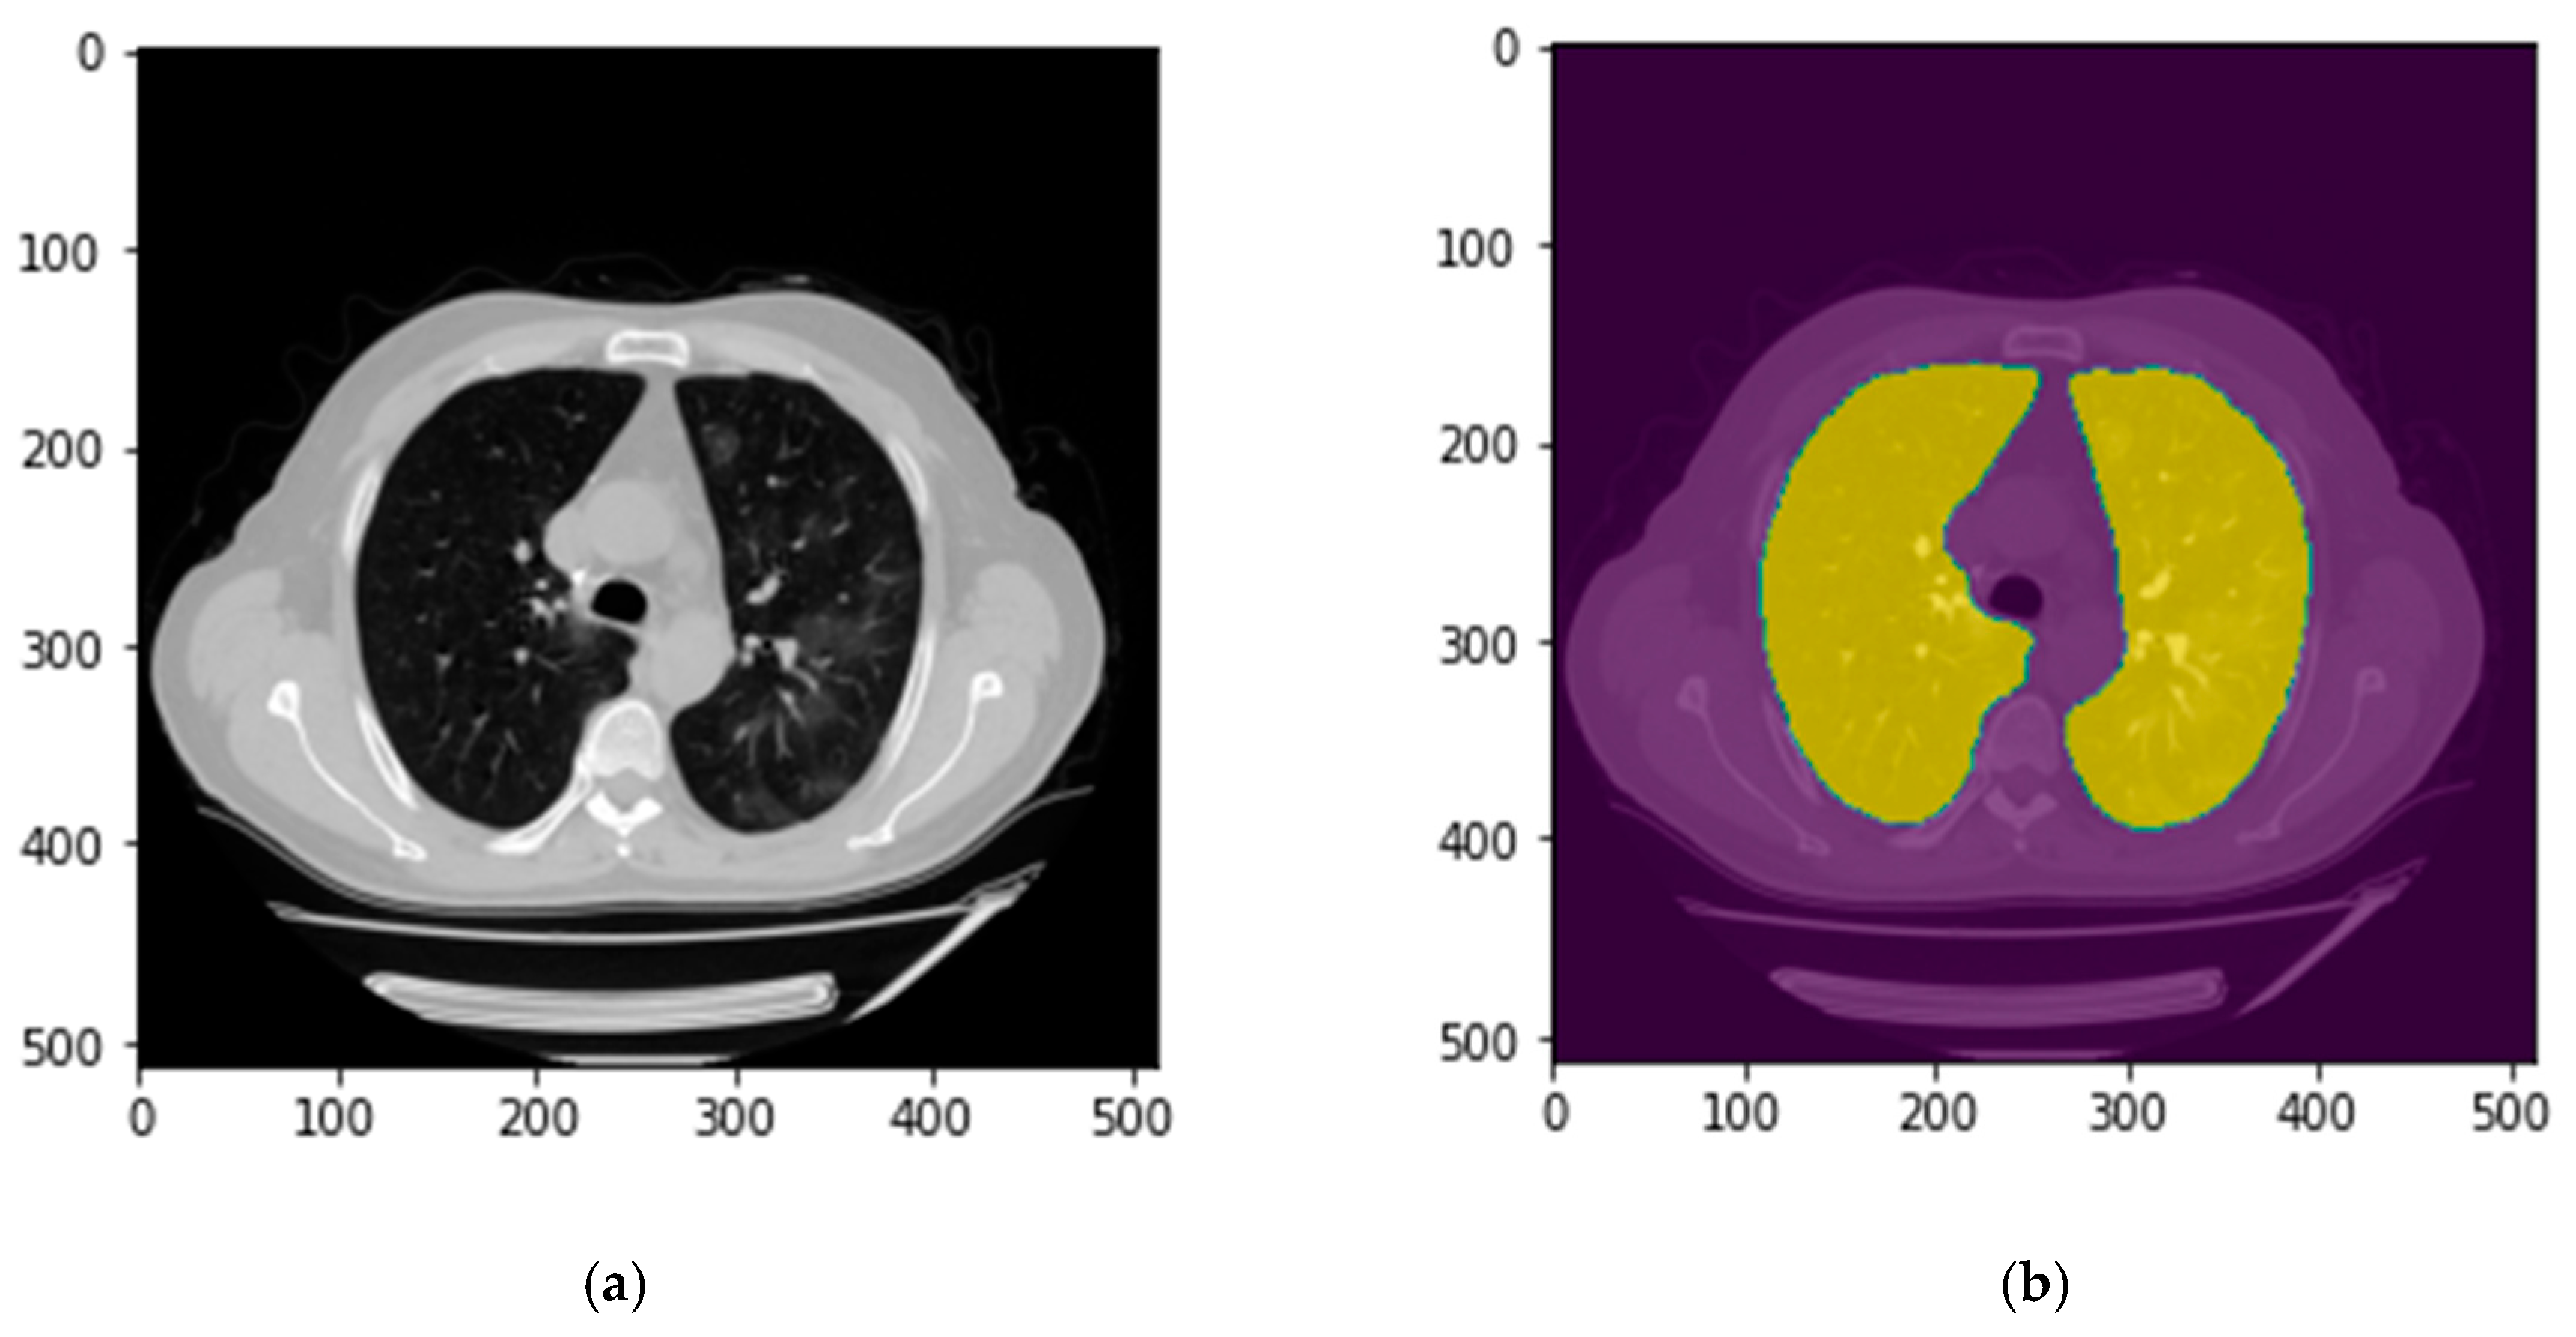

2.3.1. Lung Segmentation

2.4. Image Postprocessing and Correction